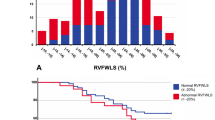

Figure 1 shows the ROC curve for RV GLS and CRP as predictors of ARDS, and the distribution of RV GLS in those who developed ARDS. The optimal cutoff value of RV GLS and CRP for predicting ARDS was 16.12 (sensitivity 77.4, specificity 61.8) and 140 (sensitivity 70.0, specificity 84.4), respectively. Figure 2 depicts Kaplan-Maier survival curves for patients with RV GLS stratified by tertile and optimal cutoff values based on ROC analysis. The ROC curves of LV GLS, LV EF, RV FAC, as predictors of CHF are shown in Fig. 3. The area under the curve for LV EF and RV FAC were greater than that for LV GLS. Best cutoff values for predicting CHF were 45 for LV EF (sensitivity 63.0, specificity 95.4) and 36.9 for RV FAC (sensitivity 61.5, specificity 83.5).